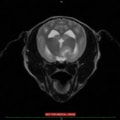

MRIの結果、頚部に脊髄空洞症を認め、頭部では水頭症および側脳室など脳内に数か所の腫瘤性病変を認めた。

頭蓋内伝播をしていることから悪性度の高い腫瘤である可能性が疑わしく、症例の頚部痛の原因と考えられる脊髄空洞症、および水頭症はこの頭蓋内腫瘤に起因する二次性発症と考えられる。

本症例の腫瘤は頭蓋内に数か所存在しており外科的切除や放射線療法は適応しにくいため、抗がん剤による化学療法の適応となった。

本症例は現在も抗がん剤(ロムスチン)による治療および脳圧降下剤などの投与であるが、症状も無く経過良好である。